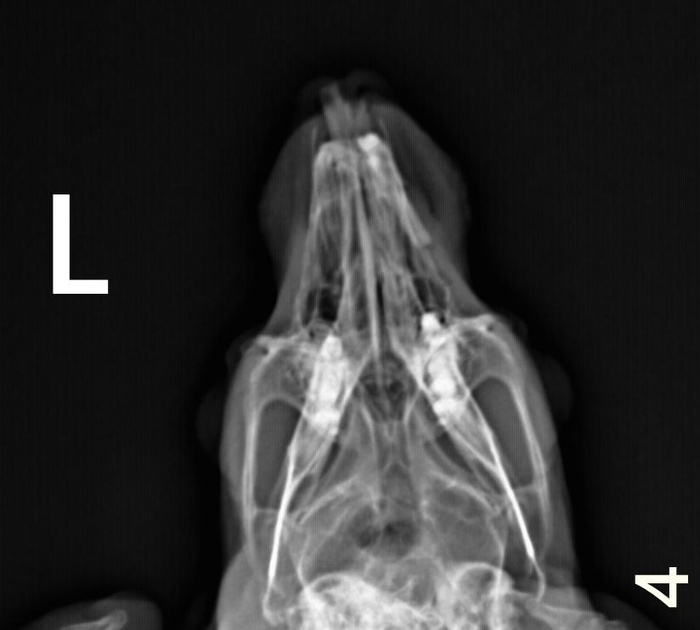

На видео ниже Анфиса с удовольствием лопает специальный корм который выглядит как прессованное сено. Сено ей настоятельно рекомендовано ветврачами ветклиники после укорачивания зубчиков, чтобы вновь не переросли. Ест и слышно как хрустит премалывая словно жерновами гранулы корма. Надеемся что это именно то что нужно и корм поможет стачивать задние зубки у Анфисы, ибо просто сено, даже разных марок, она кушать не хочет. Кормим, и не только им,  ждем результата. Что с зубами можно увидеть на рентгене.